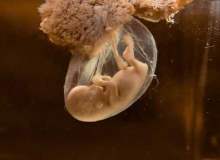

Gebelik Olmazsa Ne Zaman Doktora Gitmeli?

Toplum açısından hamile kalma süresi, 12 ay olarak kabul edilmektedir. Çünkü, fekondite denilen bir şey vardır. Yani sağlıklı bir çift için bir ayda döllenebilirlik oranı yüzde 25tir. Bu oran göz önüne alındığında, çiftlerin yüzde 85i 8-9 ay içinde